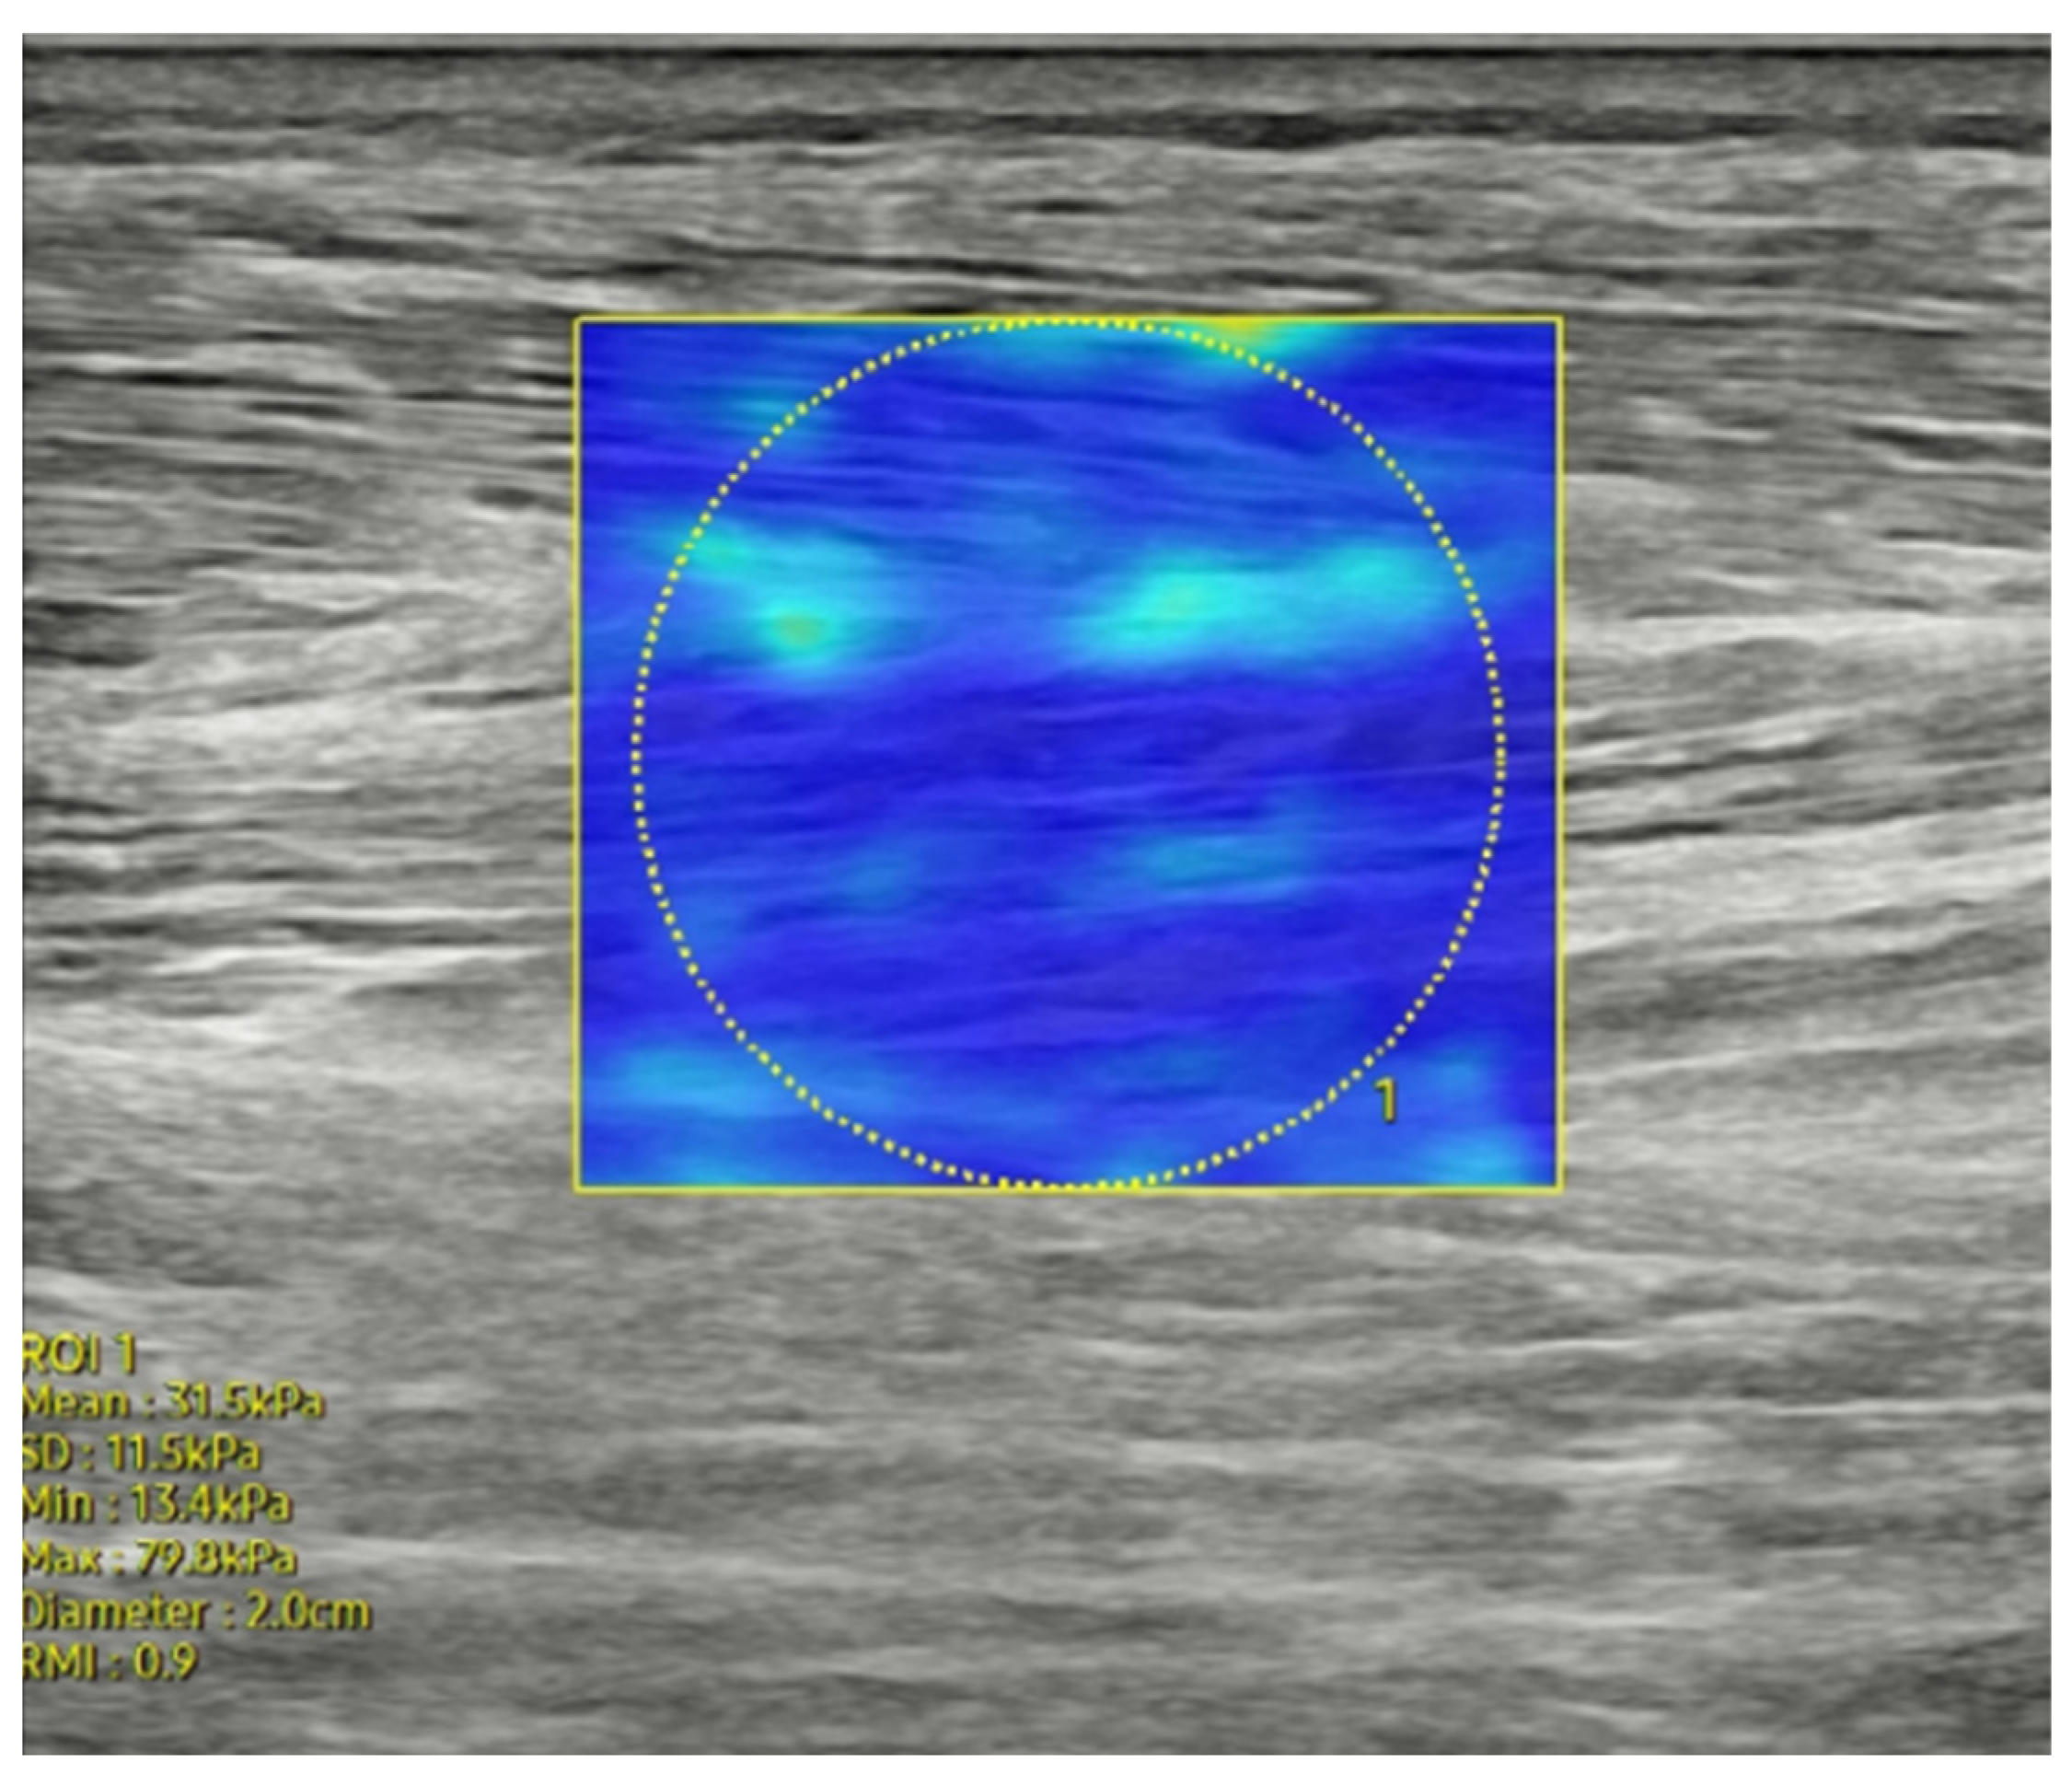

2.3.3. Muscle Stiffness

| Tibialis anterior | 27.32 ± 6.07 | 27.40 ± 6.23 | 0.931 |

| Peroneus longus | 22.01 ± 4.67 | 21.99 ± 4.57 | 0.980 |

| Medial gastrocnemius | 24.10 ± 5.06 | 22.26 ± 4.91 | 0.009 |

| Lateral gastrocnemius | 24.31 ± 5.71 | 24.09 ± 6.29 | 0.825 |

| Soleus | 37.56 ± 11.14 | 36.49 ± 10.75 | 0.507 |